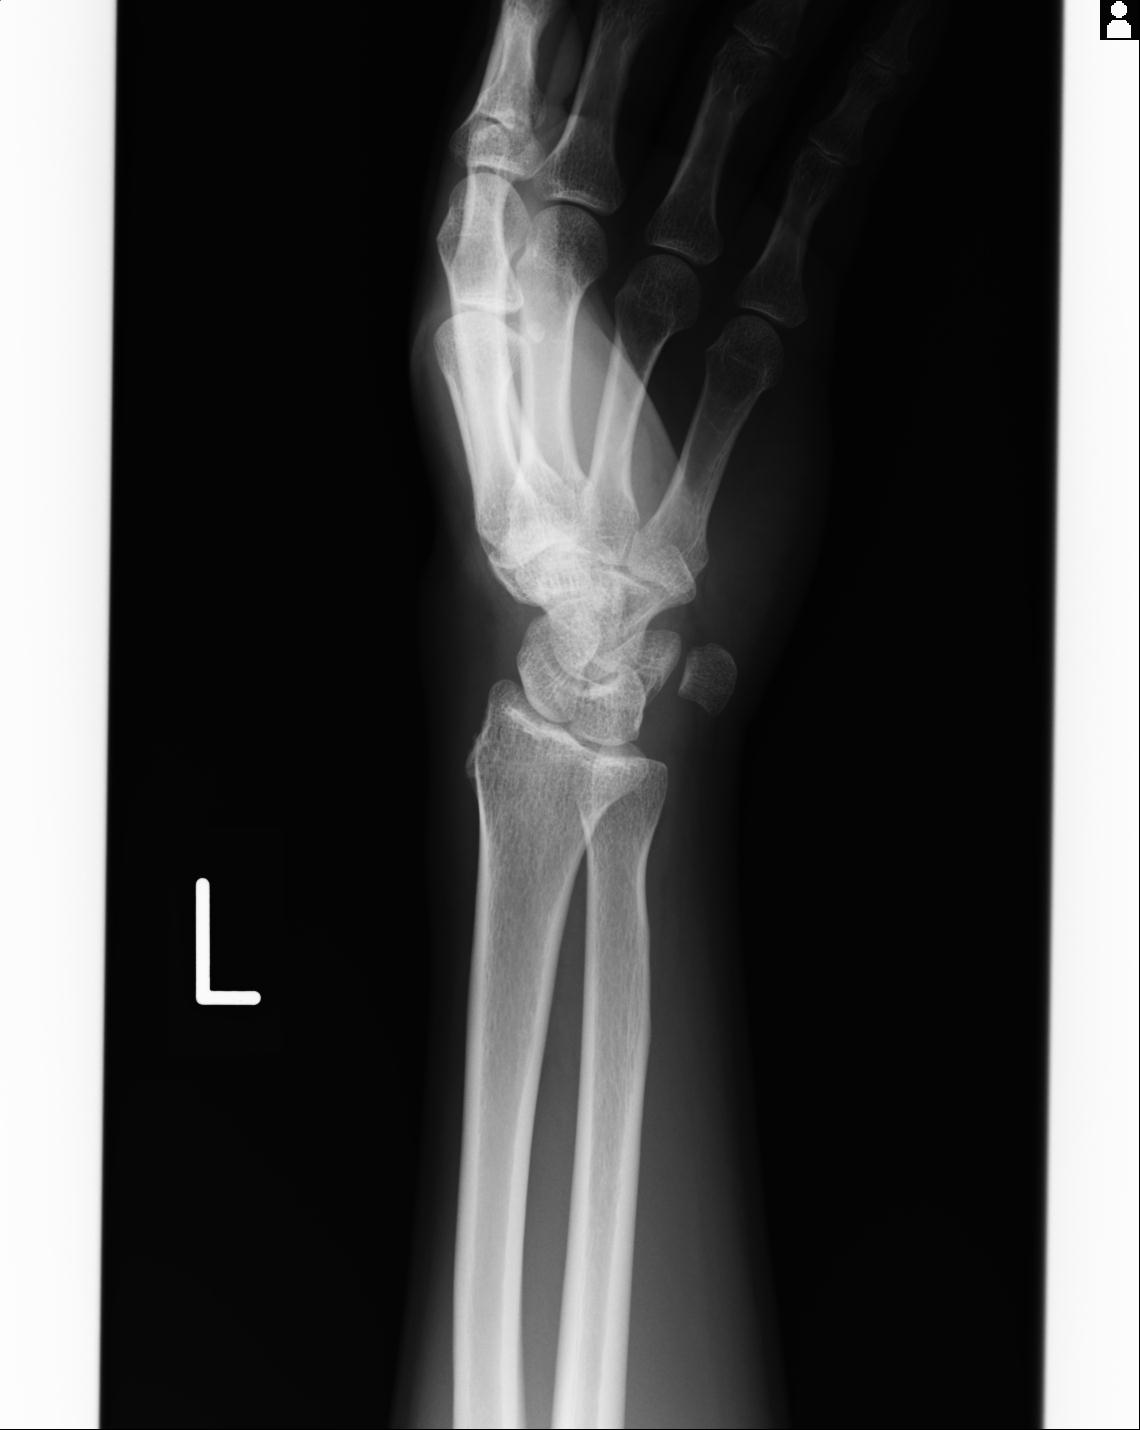

46666 1/23 両股正面+軸と右手関節 2R 76歳女性 右橈骨遠位端

46666 1/28 両股正面+軸と 1/26 右手関節 2R 76歳女性 右転子部骨折